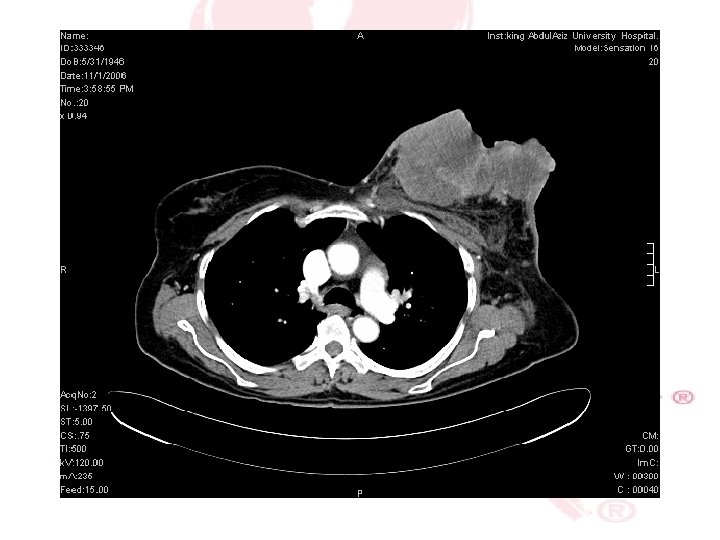

CT SCAN CHEST , ABDOMEN &PELVIS